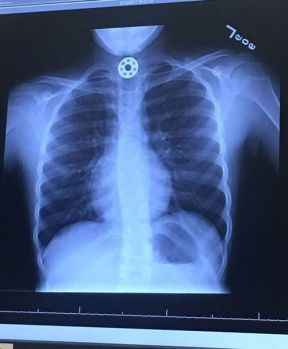

Stres çarkı bir çocuğun hayatını elinden alıyordu!

ABD'nin Houston kentinden bir kadın, kızının boğazına kaçan stres çarkına ait bir parçanın çıkarılması için ameliyat edilmek zorunda kalmasının